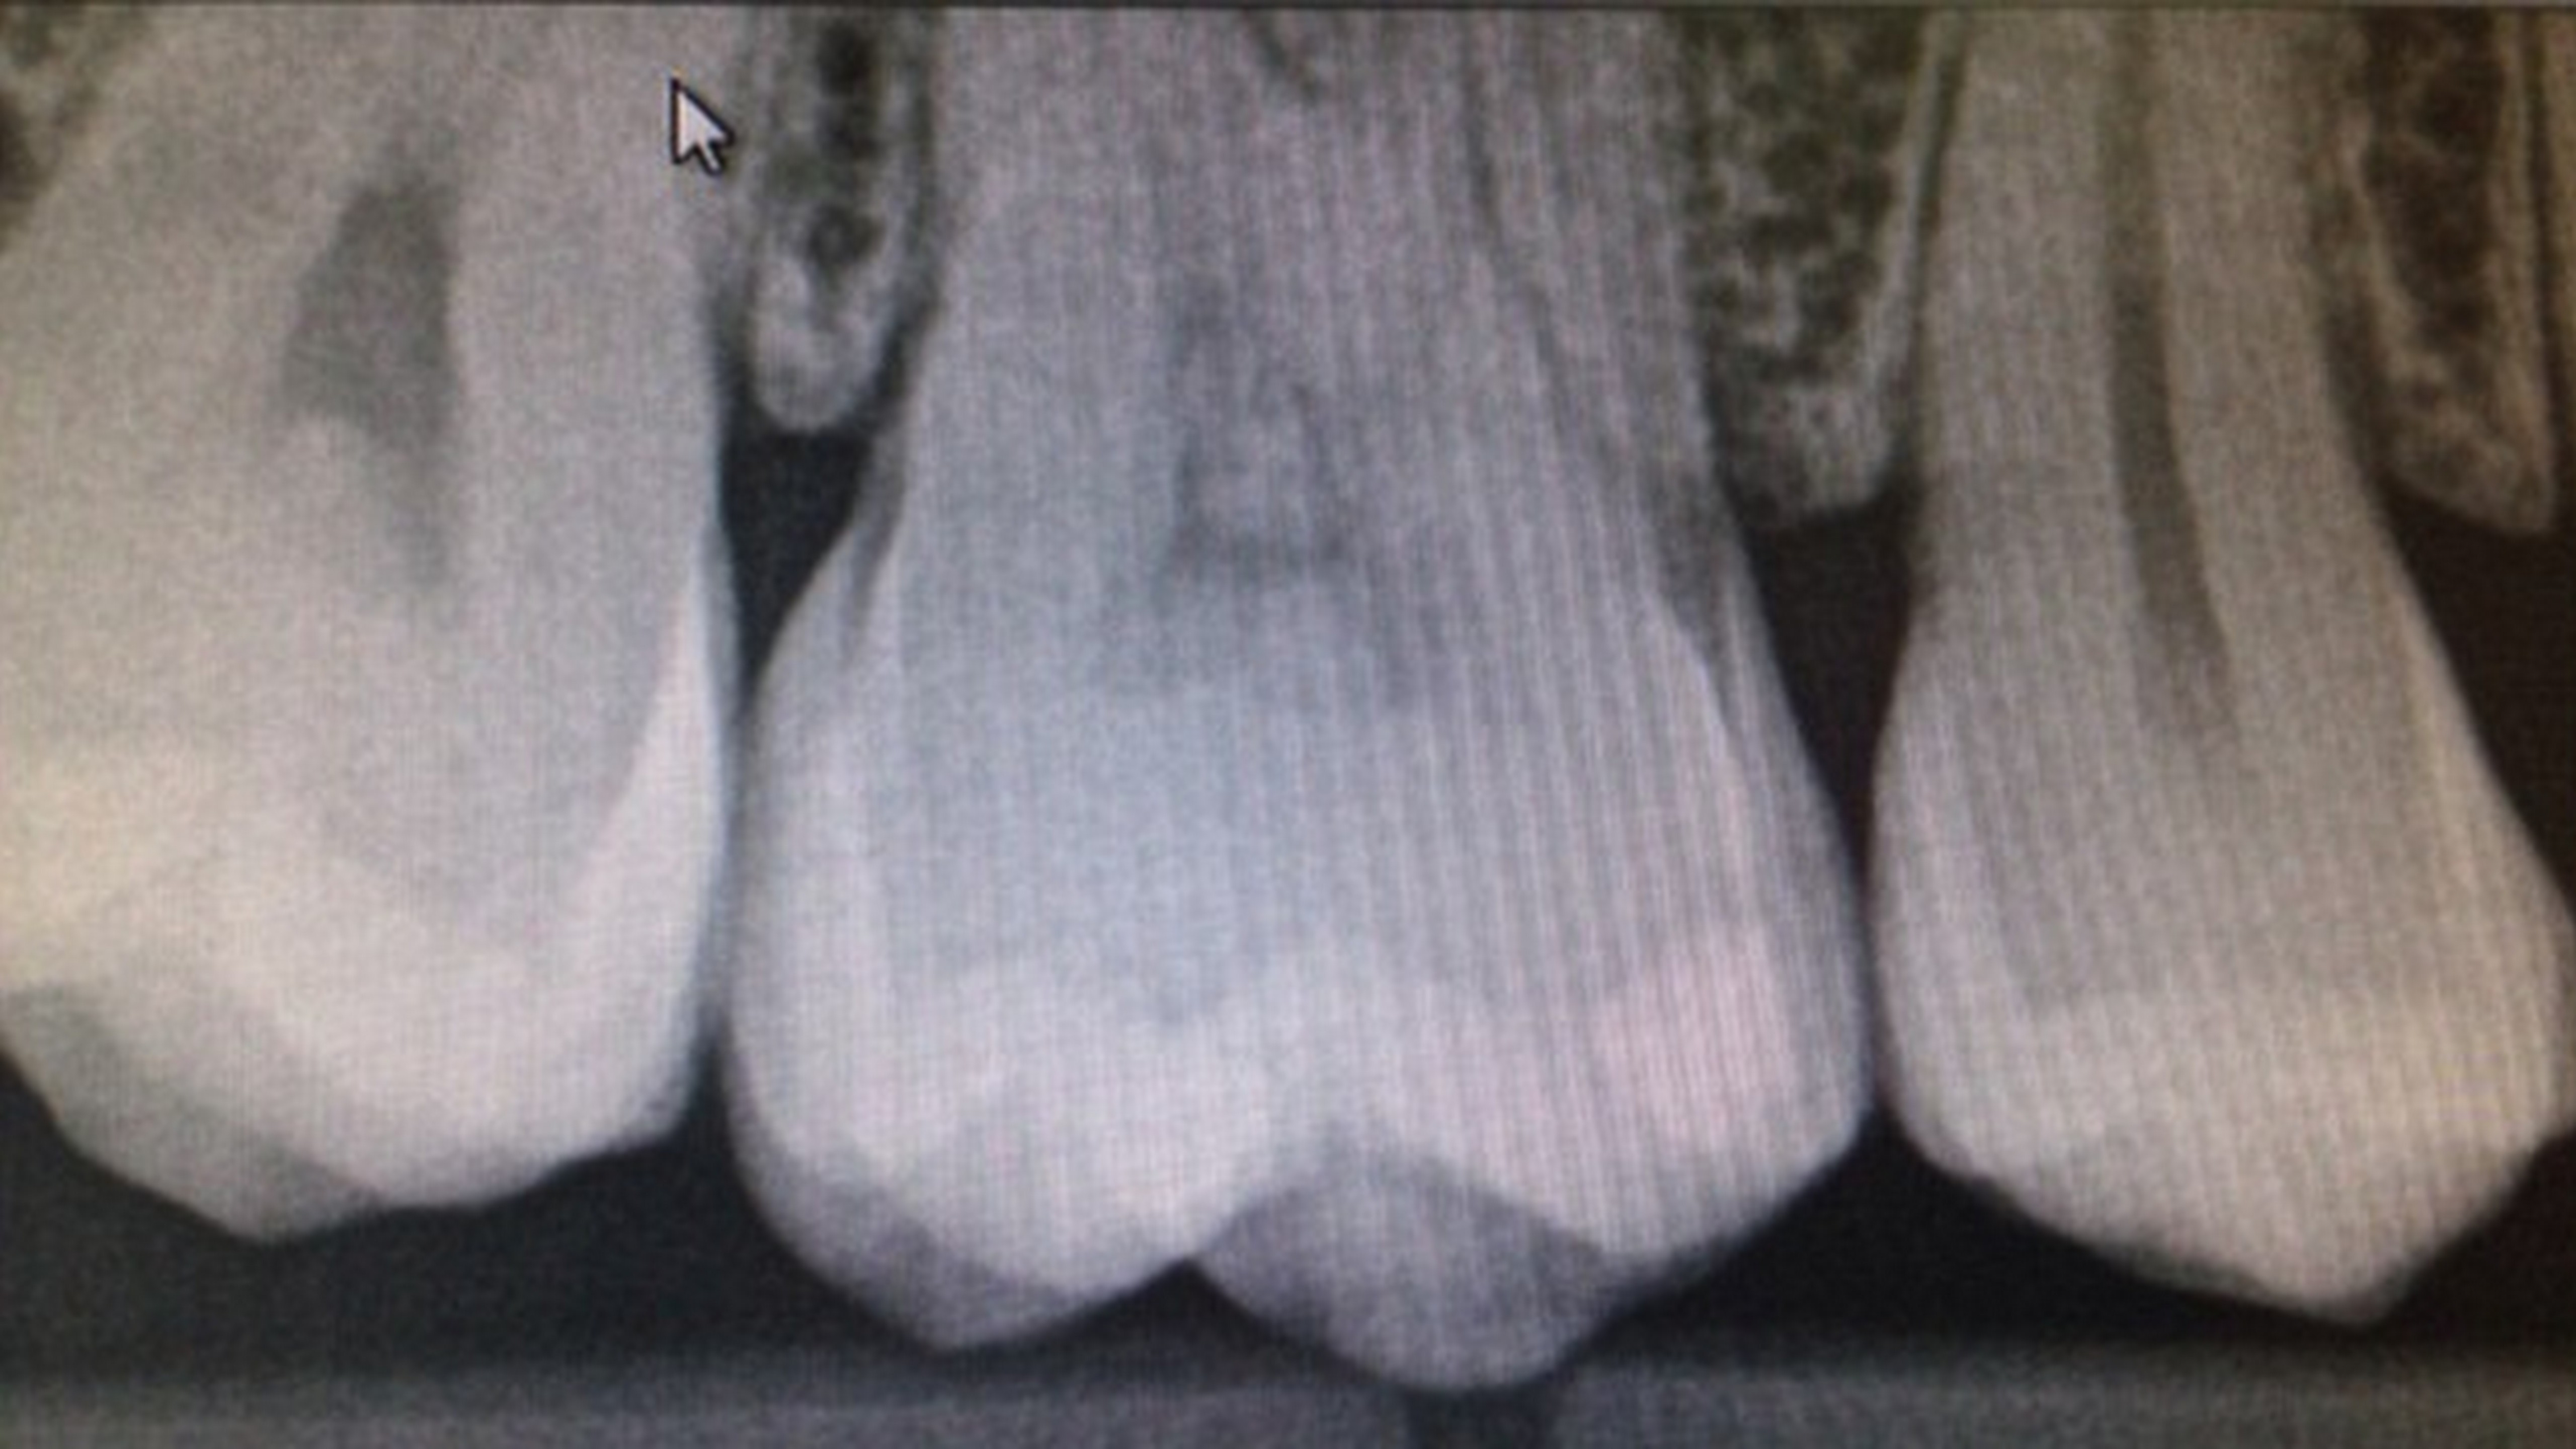

PHOENIX / Američanka Kym Ackerman mala predčasnú Veľkú noc. Pri pohľade na röntgenovú snímku svojich zubov ostala v šoku. Na jednom zube sa jej totiž zjavil obraz Ježiša.

Záhadný obraz svätého muža objavila Američanka pri rutinnej návšteve u svojho zubára. Na podobizeň Ježiša na jednej zo svojich stoličiek upozornila aj zubárku a dentálnu hygieničku, píše Daily Mail.

Hygienička so ženou súhlasila, no zubárka už bola menej nadšená. "Povedala som hygieničke, že to vyzerá šialene," hovorí Kym Ackerman o čudnom zážitku.